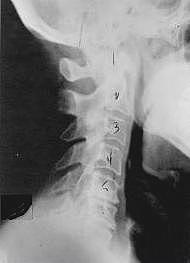

Phase One - Subluxation Degeneration

Subluxation Degeneration - Phase One Phase One Subluxation Degeneration is seen in subluxations that have been present for up to twenty years. This phase is characterized with a loss or change in the normal curve in the spine. On this example you can see that the normal forward (lordotic) curve is lost. This spine even has developed a reverse curve in the neck. The disc spaces have also begun to exhibit a slight change in shape. One good point is that the bodies of each of the vertebrae (the square part in front) still exhibits clean clear borders. Segmental motion may be abnormal but overall motion is probably not affected. Chiropractic reconstructive care for a phase one can take from 6 to 18 months. More than 80% of people with Phase One Subluxation Degeneration have no pain. Therefore, if left uncorrected, phase one continues to progress with time until it eventually reaches the next phase.